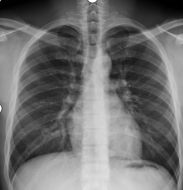

对比图如下:

x光材质怎么调【科普加油站】放射检查穿对衣服,让健康“一目了然”_https://www.jmylbn.com_新闻资讯_第5张

常规胸片(胸部X光片)

含有项链、内衣扣及钢圈遮物的胸片

因项链、文胸(钢圈、排扣)、束腰带产生了明显的白色亮影,类似的还有磁疗内裤(材质内含金属),在图像上呈现出一颗颗白色亮点,图像会干扰医生观察。